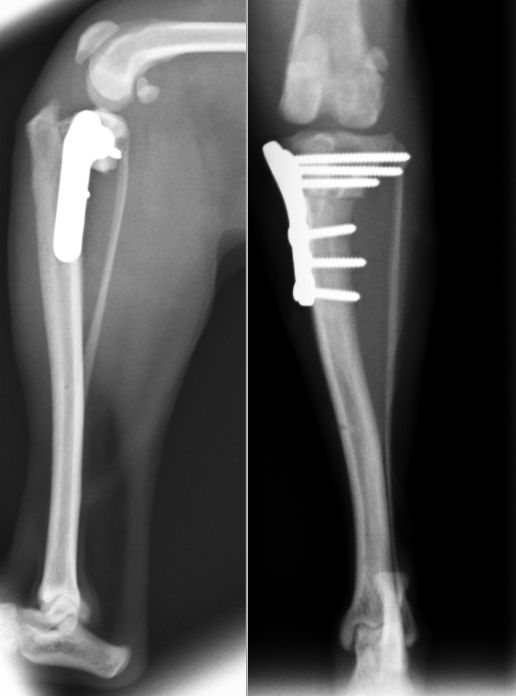

30kgの黒ラブの症例です。一番右のレントゲンが最初に行った手術です。半年後には反対側も切ってしまい、同様に手術しています(一番左)。真ん中は右の術後半年のレントゲンです。骨切部分がくっついているのがわかると思います。このように左右ともに切れてしまうケースも多いです。